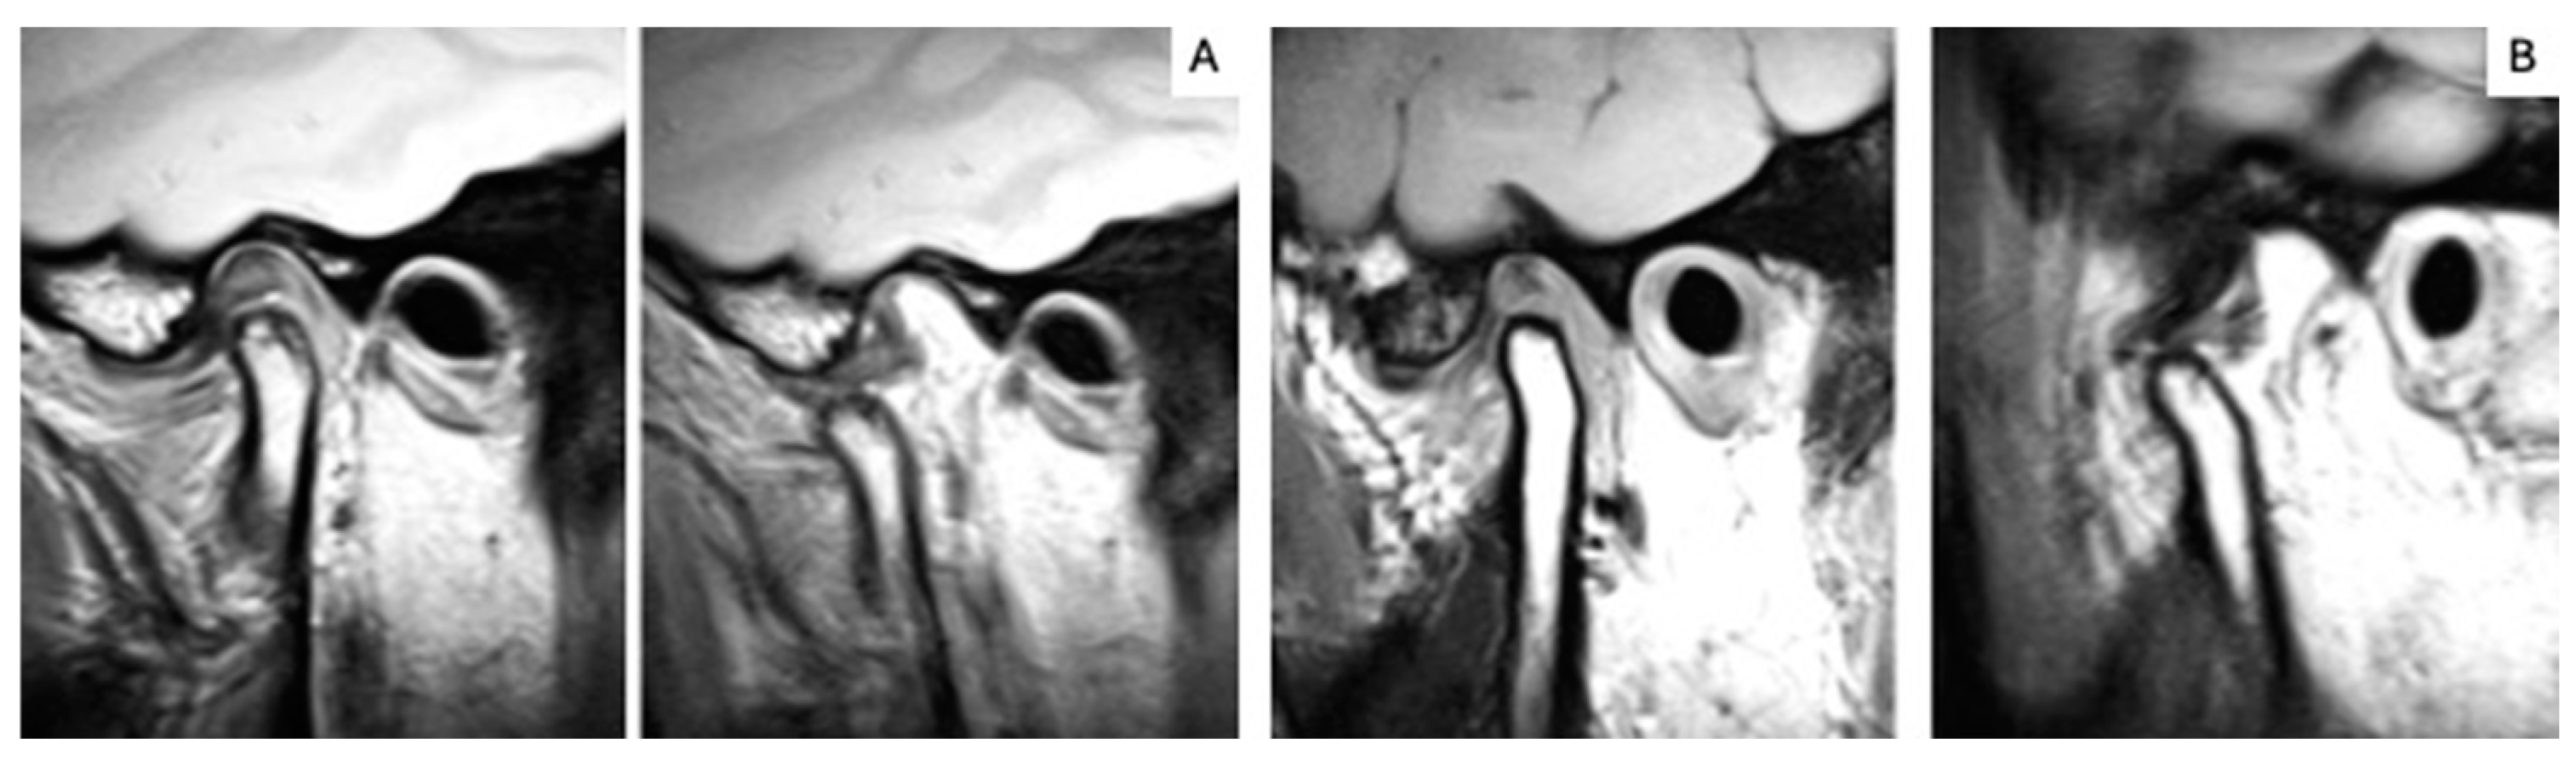

2.5. MRI Analysis